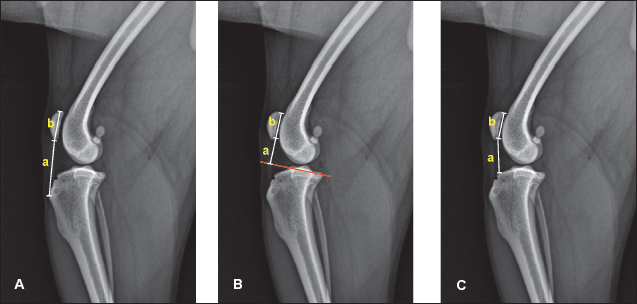

For the determination of the ISI, the lengths of the patellar ligament and the patella were determined, as described by Mostafa et al. (2008). The patellar ligament length (a) was measured from the distal patellar pole to the point where the ligament inserts onto the tibial tuberosity (Fig. 1A). The length of the patella (b) was measured between its proximal and distal poles. The ISI was calculated as the ratio a/b (Insall and Salvati, 1972).

For the measurement of the BPI, a line passing through the tibial plateau was initially drawn (Blackburne and Peel, 1977). BPI is calculated as a ratio of the height of the distal pole of the articular surface above this tibial plateau line (a) to the patellar articular surface length (b) (Fig. 1B).

Fig. 1. Measurement of indices of proximodistal patellar position. A. The ISI is measured as the ratio of the patellar tendon length (a) to the distance between proximal and distal patellar poles (b); B. The BPI is the ratio of the height of the distal pole of the articular surface above the tibial plateau line (a) to the patellar articular surface length (b); and C. The CDI is determined as a ratio of the distance between the distal point of the patellar articular surface (a) and the cranioproximal margin of the tibia, divided by the patellar articular surface length (b).

For the calculation of the CDI, the distance from the distal edge of the patellar articular surface to the cranioproximal margin of the tibia (a) was divided by the patellar articular surface length (b) (Caton et al., 1982).